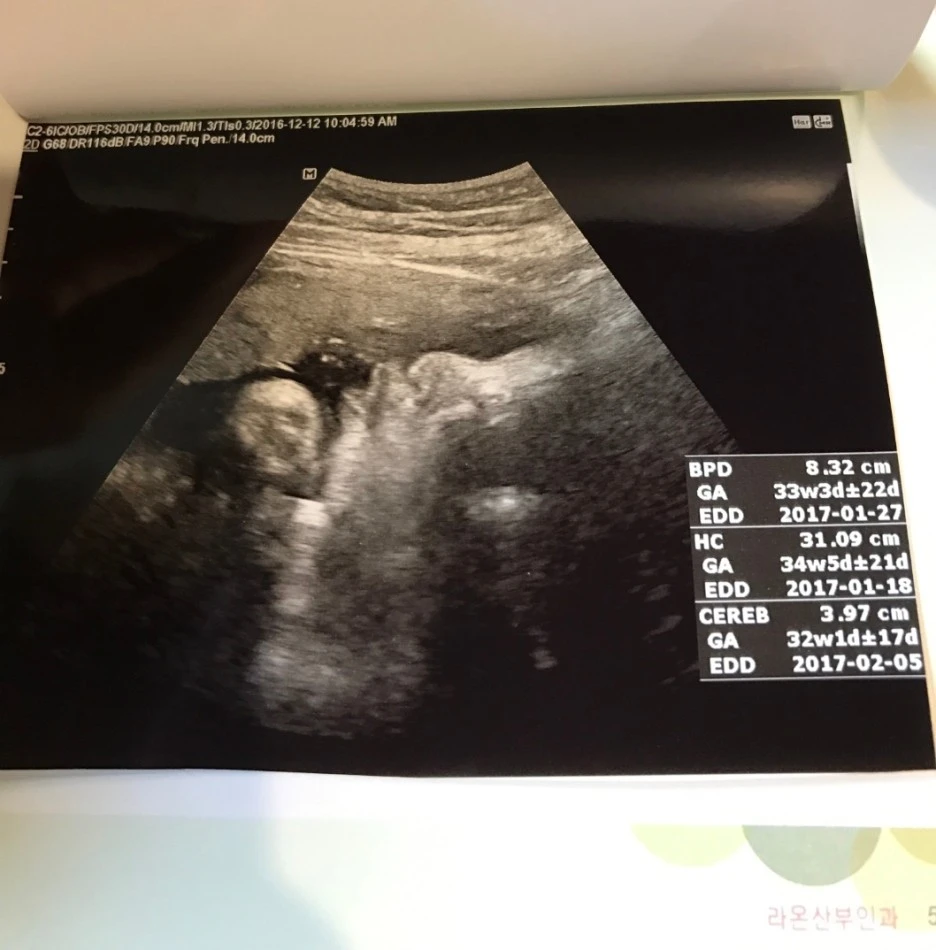

SE-4fce2f10-5b50-4045-83a2-788956db4efe.jpg?type=w1